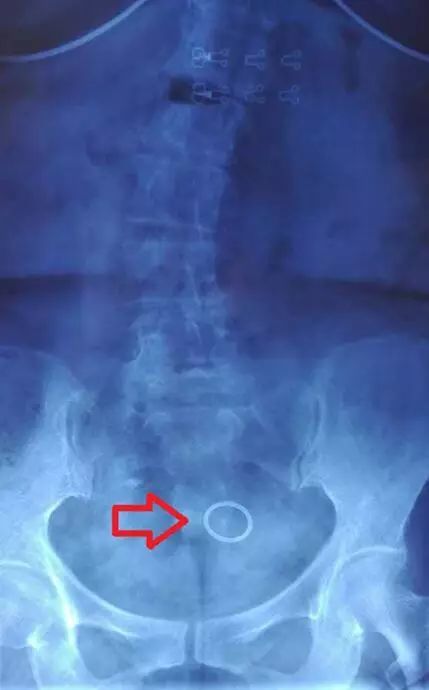

那么,节育环是否会产生伪影呢?这一点确实是真的,它确实会产生一些伪影并影响周围组织的图像质量。但是这种影响是局限在盆腔的,对于腰椎以及颈椎的核磁共振不会产生影响。以我今天门诊的一名50岁女性椎间盘突出患者为例,大家可以看到,X线片上显示盆腔里有金属节育器,在她的磁共振片子里,节育器确实产生了少量伪影,但是椎间盘突出的部位仍清晰可见,伪影未造成任何干扰,丝毫不影响医生的读片判断。